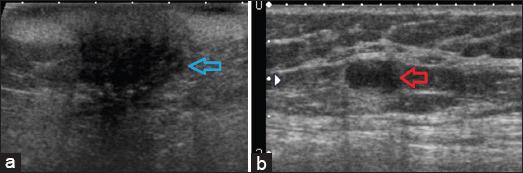

A total of eight cases were identified, out of which seven were females. The most common presentation consisted of the presence of metastatic nodules which were seen in 62.5% (five out of eight) of the patients. Other features consisted of erythematous or plaque-like skin thickening on clinical examination, increased density with indistinct margins seen on a mammogram and diffuse oedematous changes in the skin with small irregular mass or infiltration into subcutaneous tissues were visualised on ultrasound and CT studies.